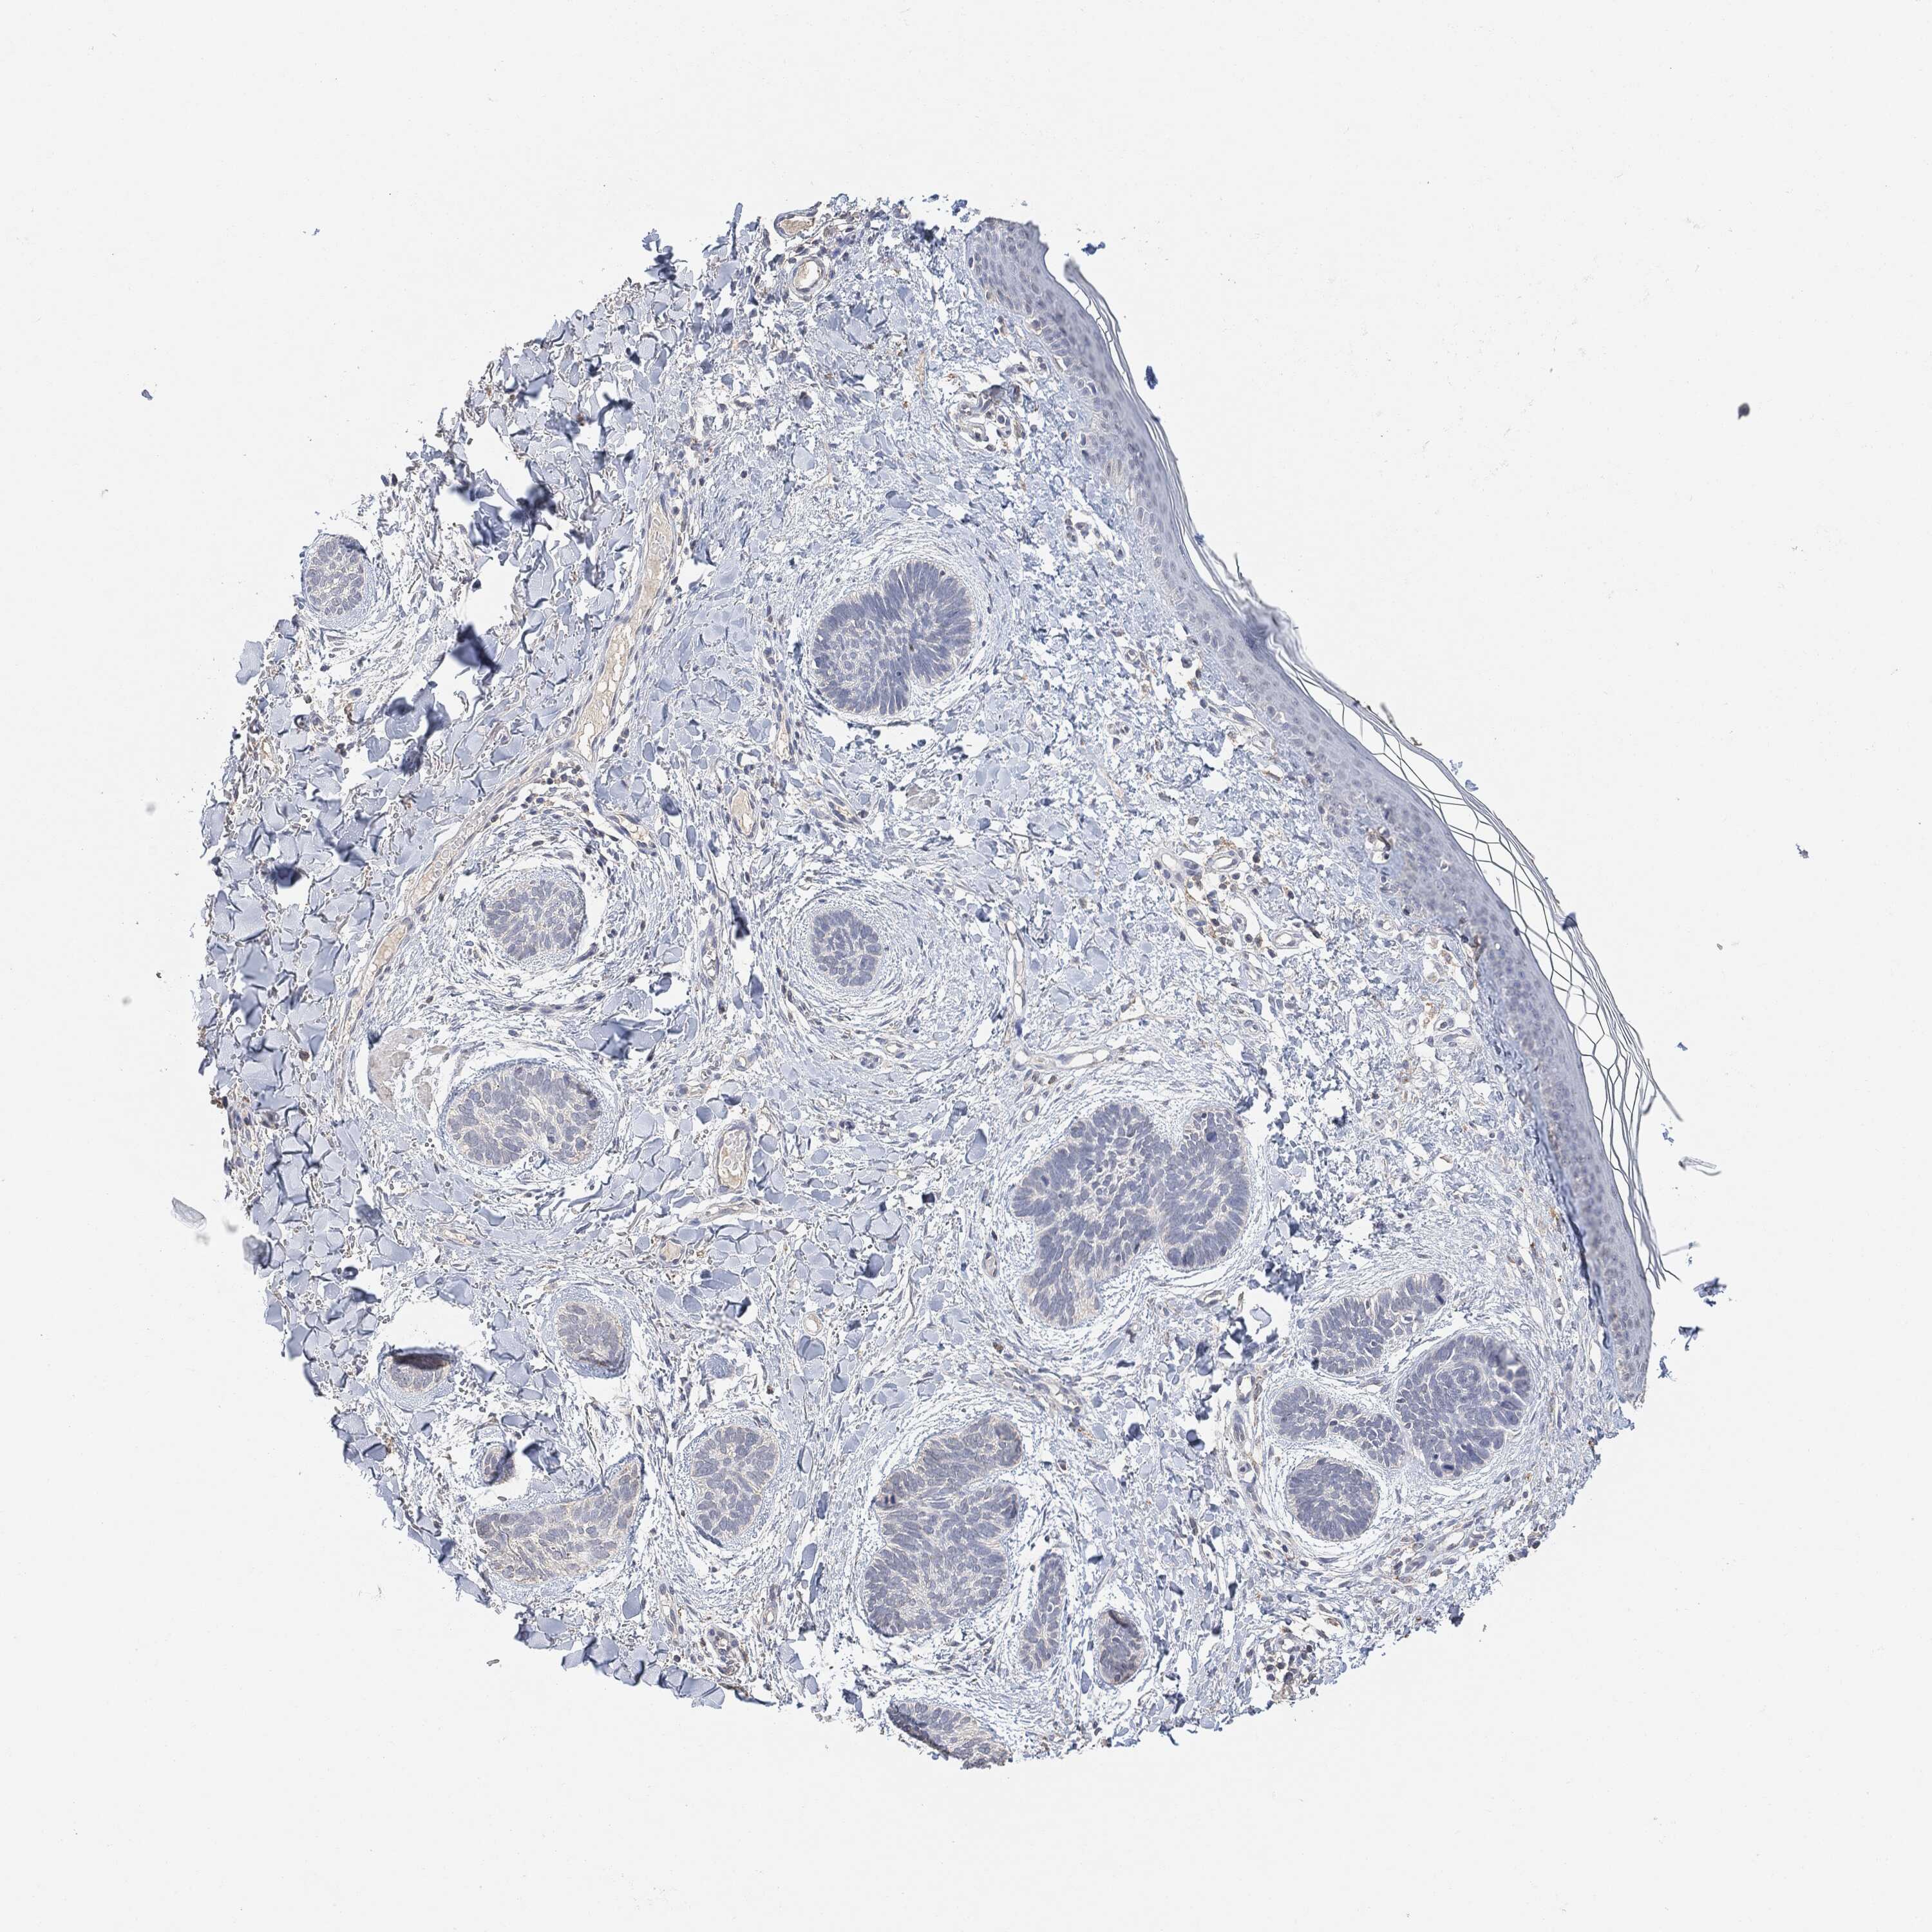

CANCER SKIN CANCER Show tissue menu

SKIN CANCER - Protein expressioni

A mouse-over function shows sample information and annotation data. Click on an image to view it in a full screen mode. Samples can be filtered based on level of antibody staining by selecting one or several of the following categories: high, medium, low and not detected. The assay and annotation is described here.

Each image is clickable and will lead to virtual microscopy that enables deeper exploration of all samples and also displays staining intensity scores, fraction scores and subcellular localization as well as patient and tissue information for each sample.

Squamous cell carcinoma in situ, NOS